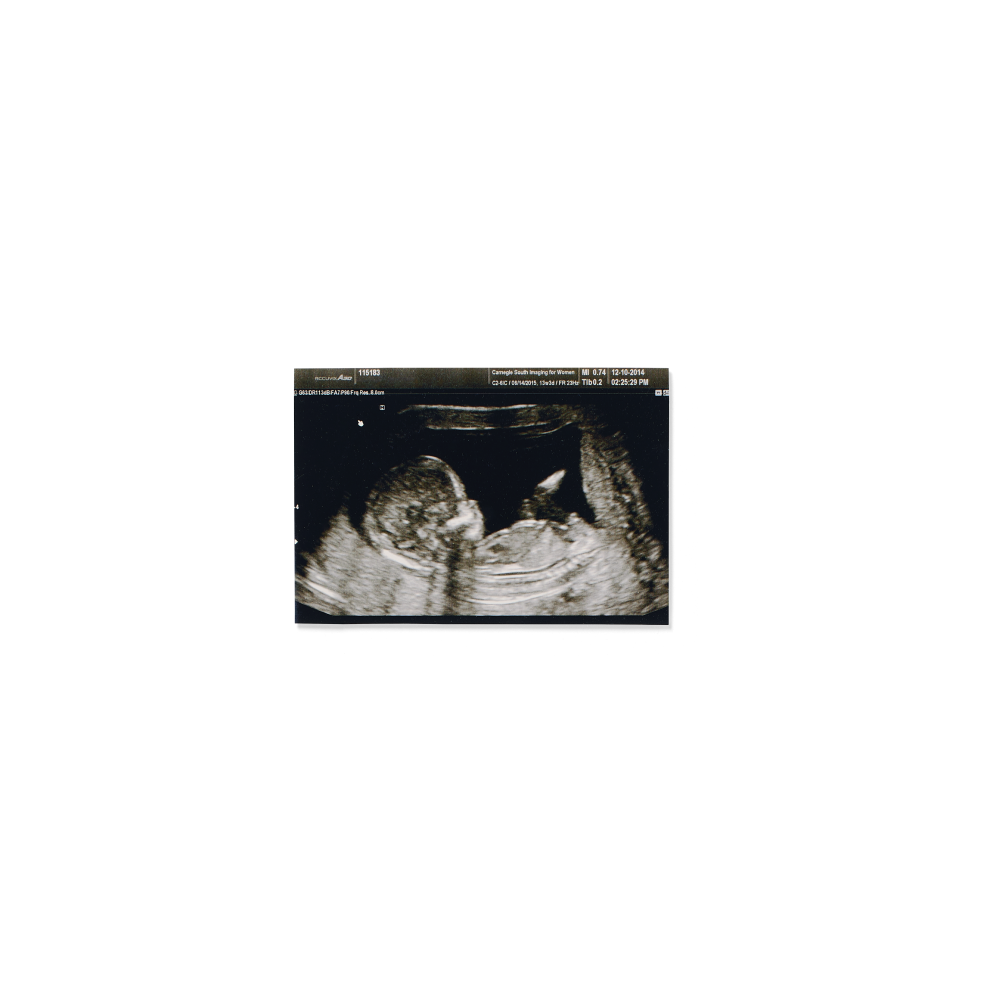

First peeks